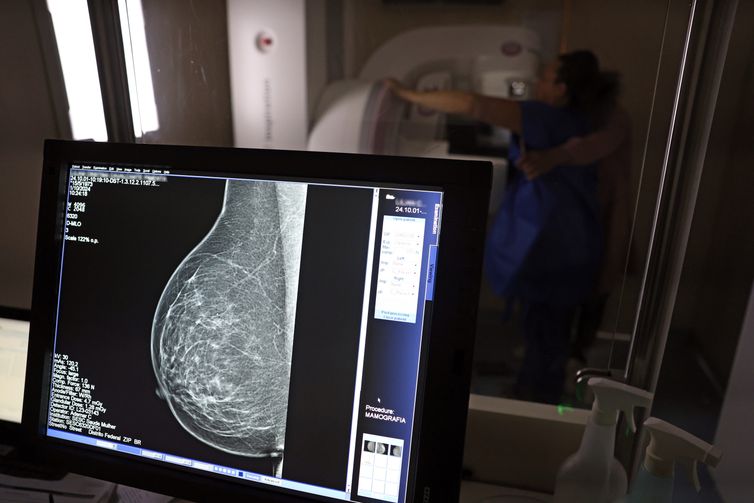

Um dos principais critérios é a realização de rastreamento organizado, ou seja, a convocação das usuárias para realizarem exames regularmente, mesmo sem sintomas. No caso do câncer de mama, a cartilha seguiu o protocolo do Ministério da Saúde e do Instituto Nacional do Câncer (Inca): mamografias a cada dois anos para as mulheres com idades entre 50 e 69 anos.

Para as entidades médicas, a mamografia deve incluir essas pessoas, porque o diagnóstico de câncer em pessoas assintomáticas, a partir de exames de imagem, demanda tratamentos que impactam menos a qualidade de vida da paciente, e tem menos risco de recidivas, metástases e mortalidade.

No Brasil, a cobertura da mamografia ainda é um desafio. A última Pesquisa Nacional de Saúde, realizada pelo Instituto Brasileiro de Geografia e Estatística (IBGE) em 2019, mostrou que menos de 60% das mulheres de 50 a 69 anos tinham feito mamografia há menos de dois anos da data da entrevista.